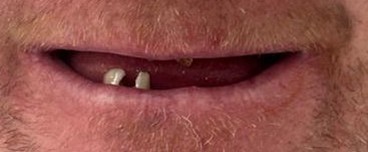

The Patient’s Challenge

This patient presented with significant dental concerns affecting both oral function and smile appearance. Everyday activities such as eating, speaking, and smiling comfortably had become increasingly difficult.

Why He Came to See Us

The patient visited Sayers Dental feeling frustrated with his remaining broken teeth and was ready for a fresh start. He wanted to eat comfortably, improve his appearance, and regain the confidence to smile again.

For him, this journey was about more than just teeth — it was about restoring quality of life, comfort, and self-esteem.